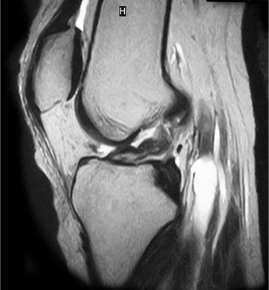

• ACL 손상 방사선 사진2